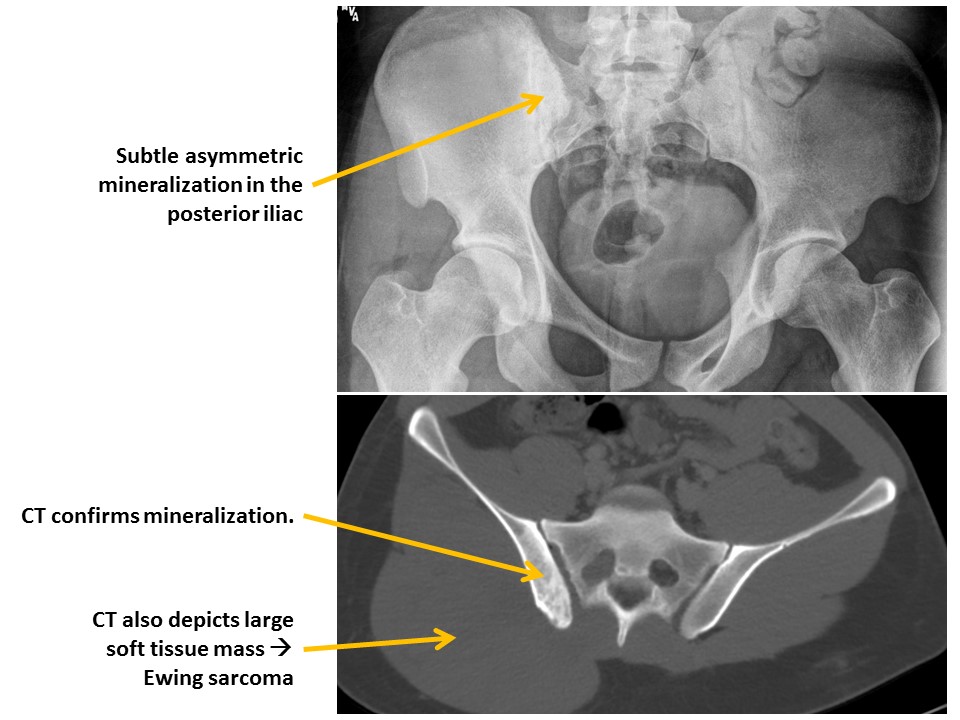

MISCELLANEOUS OSSEOUS

The osseous mineralization is diffusely abnormal. [Yes/No]

An additional osseous lesion is present. [Yes/No]

SOFT TISSUES